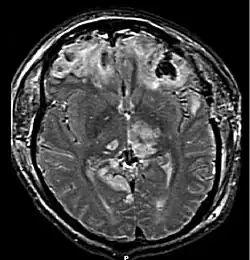

Diffuse injury manifests with little apparent damage in neuroimaging studies, but lesions can be seen with microscopy techniques post-mortem,[25][26] and in the early 2000s, researchers discovered that diffusion tensor imaging (DTI), a way of processing MRI images that shows white matter tracts, was an effective tool for displaying the extent of diffuse axonal injury.[27][28] Types of injuries considered diffuse include edema (swelling), concussion and diffuse axonal injury, which is widespread damage to axons including white matter tracts and projections to the cortex.[29][30]

Magnetic resonance imaging (MRI) can show more detail than CT, and can add information about expected outcome in the long term.[23] It is more useful than CT for detecting injury characteristics such as diffuse axonal injury in the longer term;[10] however, MRI is not used in the emergency setting for reasons including its relative inefficacy in detecting bleeds and fractures, its lengthy acquisition of images, the inaccessibility of the patient in the machine, and its incompatibility with metal items used in emergency care.[23] A variant of MRI since 2012 is high-definition fiber tracking (HDFT).[81]